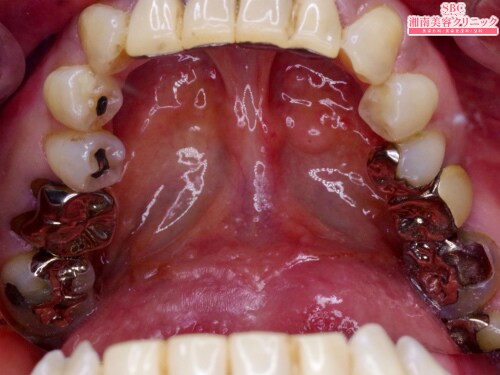

施術前

術前は奥歯に目立つ銀歯。

この銀歯を金属の土台とともに全て除去して白い歯に。

歯科技工士立会いで作製するプレミアムダイヤモンドセラミックを装着。

白く綺麗な歯に改善しました。